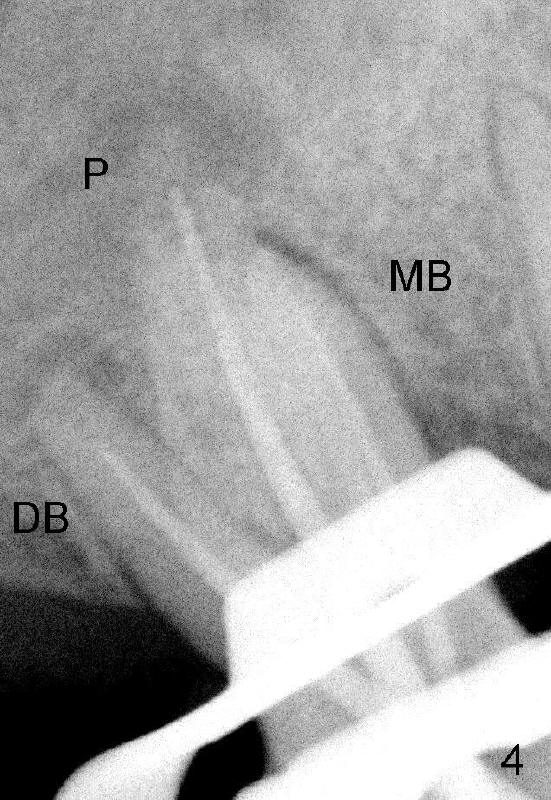

打开髓腔,MB根管还是通不到根尖,突然意识到自己有个大缺点:看片不认真。不得不脱下手套,走到办公室,关掉电灯,在暗光下,再次研究MB根以及根管特点:它们都向颊侧弯曲(图二箭头)!研究CT另外一个断面(图三)发现MB根和根管也往远中弯曲。方向明确后,预先弯曲扩大针,尽管笨手笨脚,最终目的还能达到,图四显示主牙胶尖插入:MB:

20/.06; DB: 30/.06; P: 40/.06,与图五,图六对比。总之,没有CT,事倍功半。